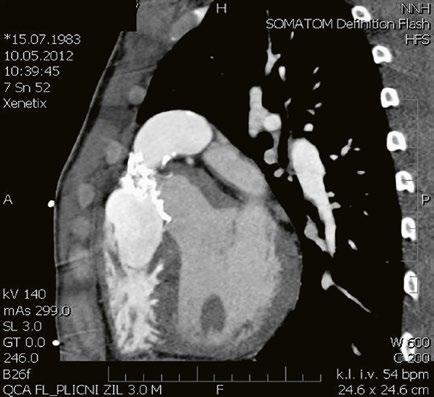

Obr. 45.11 CT angiografie, defekt typu sinus venosus superior je označen hvězdičkou, anomální pravá horní plicní žíla ústící do horní duté žíly je označena šipkou

PS – pravá síň, LS – levá síň

Při podezření na anomální návrat plicních žil je vhodnější doplnit CT angiografii nebo magnetickou rezonanci (Obr. 45.11, Obr. 45.12). Při podezření na závažnější plicní hypertenzi je indikovaná pravostranná katetrizace.

Obr. 45.12 CT angiografie s 3D rekonstrukcí u pacientky s defektem typu sinus venosus superior a s parciálním anomálním návratem dvou pravostranných plicních žil z horního a středního laloku do horní duté žíly, pravá dolní plicní žíla ústí normálně do levé síně